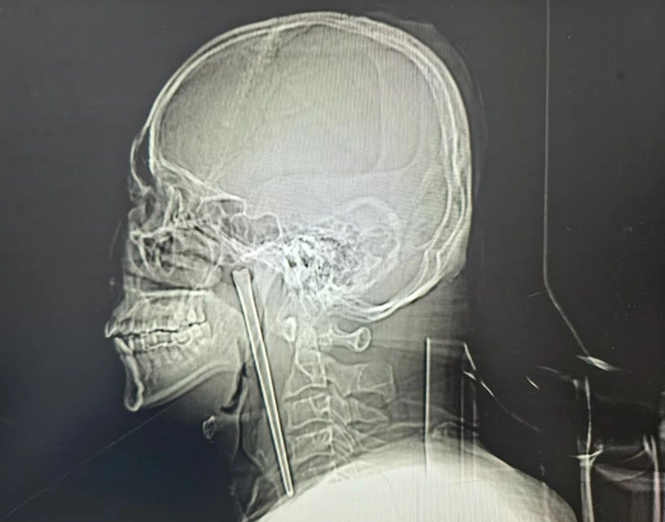

В итоге медики приняли решение провести малоинвазивную операцию. Специалистам удалось аккуратно извлечь металлическую палочку через ротовую полость, избежав более травматичного вмешательства.